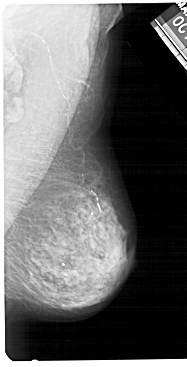

A_1393_1.LEFT_CC

LEFT_CC LINES 4891 PIXELS_PER_LINE 2611 BITS_PER_PIXEL 12 RESOLUTION 43.5 OVERLAY